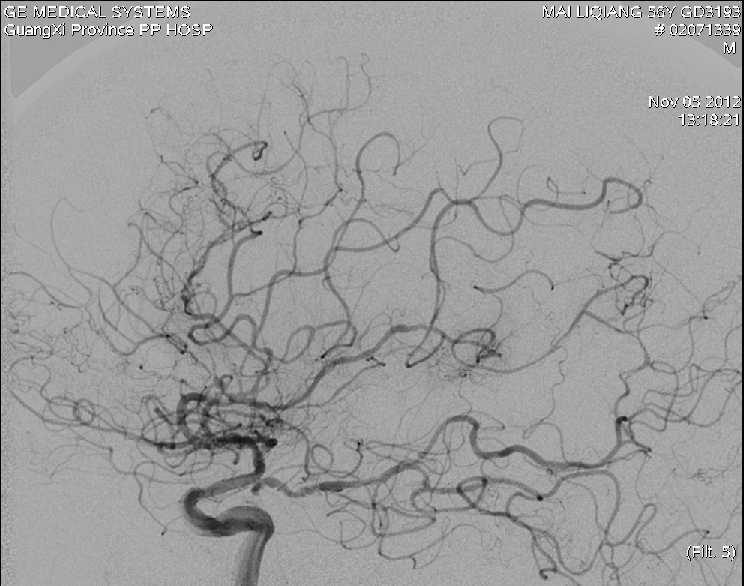

SAH增高脑血流减少缺血,同时可能引起颅内压增高,到底提高脑灌注是利大于弊还是弊大于利?

提高灌注压的治疗多少有利?

缺血还是充血?

TCD告诉你!